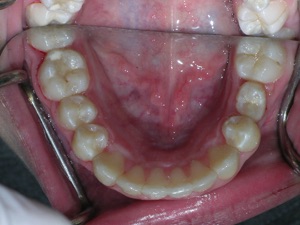

In this case, a young woman came to us with a desire to straighten her teeth. We elected to do Invisalign treatment with some enamel reduction and some dental arch expansion. Take a look...

Here she is on the day of appliance removal. You can see how the crossbite on the right has improved, as well as the lower front teeth crowding. Note that we elected to leave the lower second premolar in it’s rotated form.